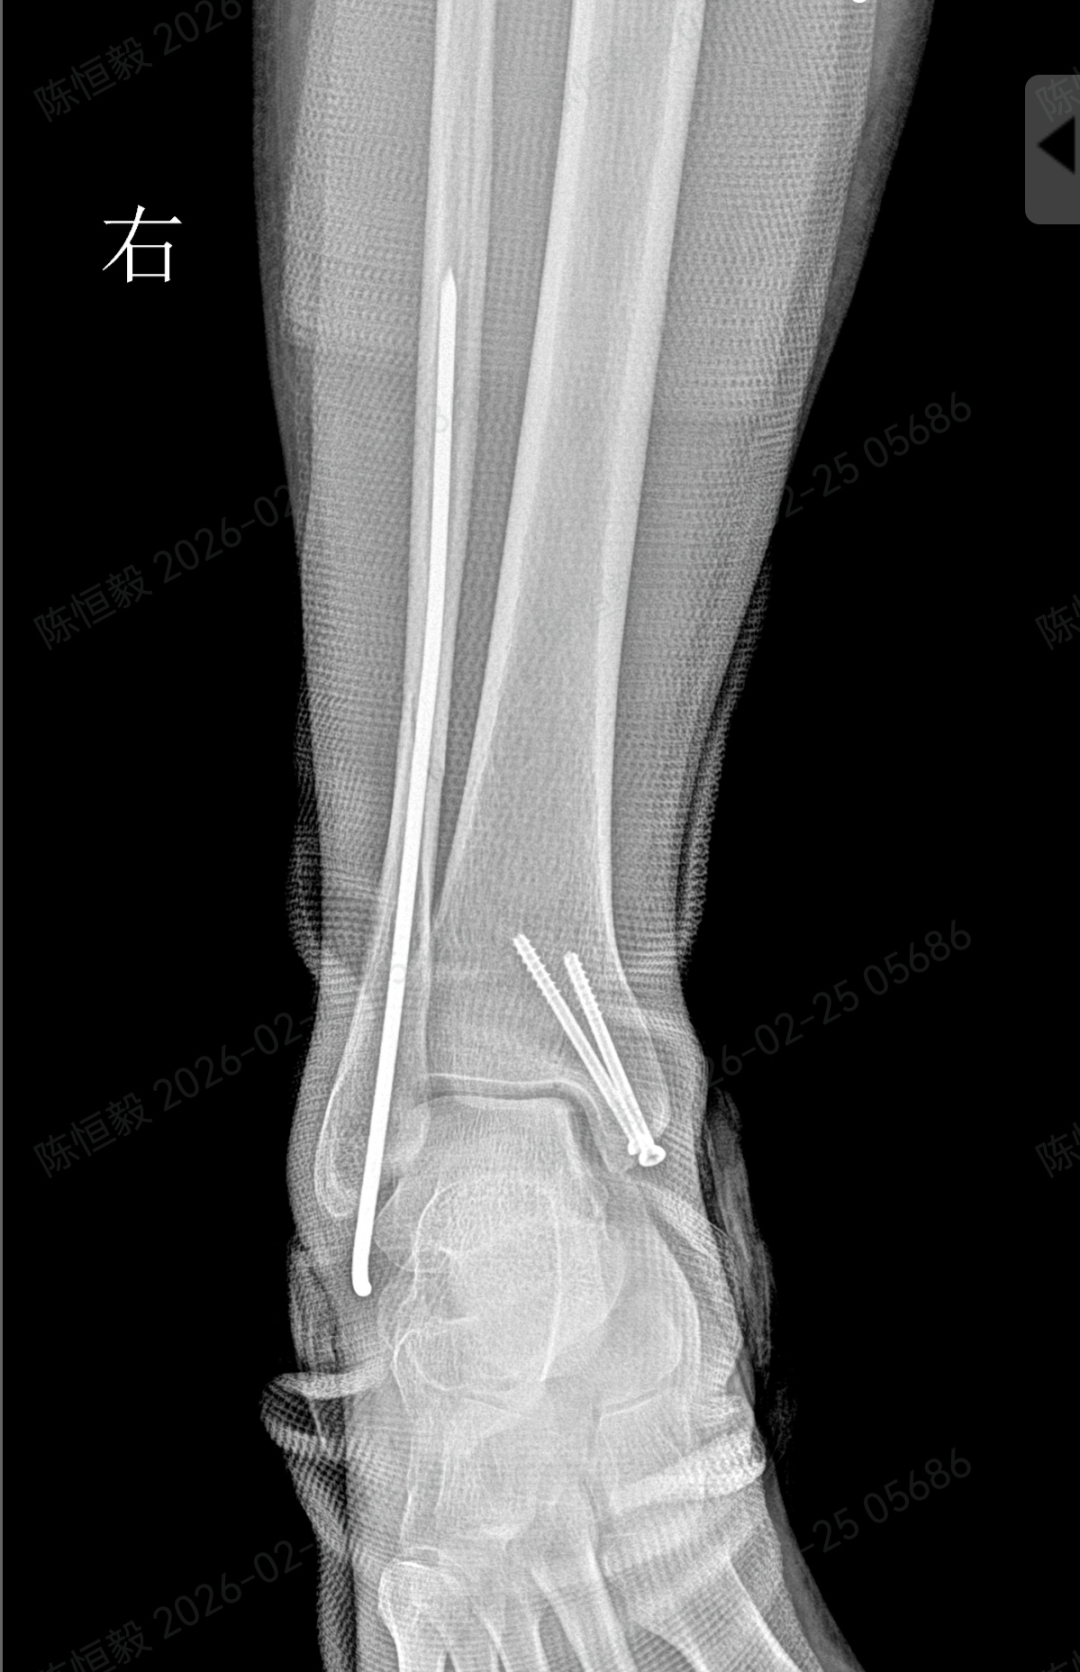

针对王女士的踝关节骨折情况,由副主任医师陈涛主刀,足踝外科团队为其实施了关节镜辅助下机器人导航微创闭合复位内固定术。

通过 5 毫米小切口将关节镜探入关节腔内,清理腔内淤血与致炎因子,清晰观察骨折块移位及关节软骨损伤情况;

在关节镜直视下,使用微创器械将骨折块复位至解剖位置,恢复关节面平整;

依托机器人导航系统,规划螺钉置入通道,避开关节面与重要组织;

最后通过另外两个 5 毫米的小孔置入空心螺钉,完成骨折端的稳定固定。

整个手术仅通过三个 5 毫米的小切口完成,最大程度降低了手术创伤。

对于踝关节骨折的诊疗而言,关节面复位的精准度直接关系到远期恢复效果,若复位存在偏差,可能增加创伤性关节炎、慢性疼痛、关节功能障碍等问题的发生概率。

本次诊疗中,在关节镜直视下确保骨折部位实现解剖复位,同时对检查中发现的合并软骨损伤进行了同步处理,为关节的后续恢复提供了保障。